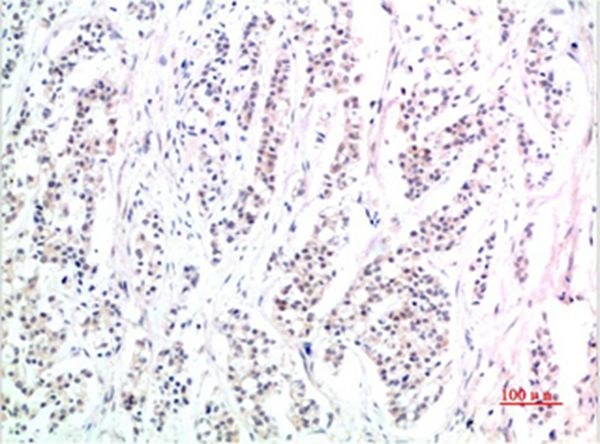

Immunohistochemical analysis of paraffin-embedded Human Skin Tissue using Phospho-Smad3(S425)Mouse mAb diluted at 1:200

,

Immunohistochemical analysis of paraffin-embedded Human Stomach Carcinoma Tissue using Phospho-Smad3(S425) Mouse mAb diluted at 1:200